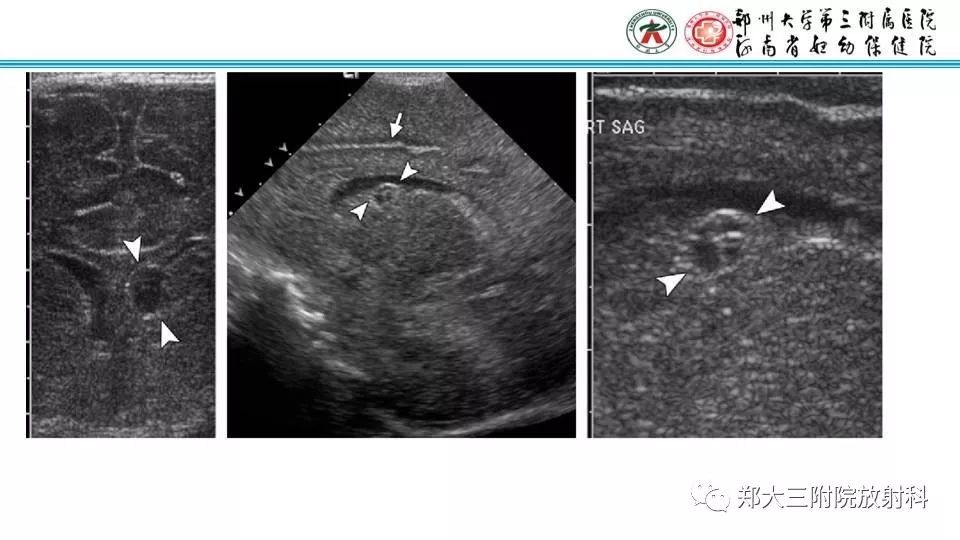

【PPT】室周假性囊肿-2